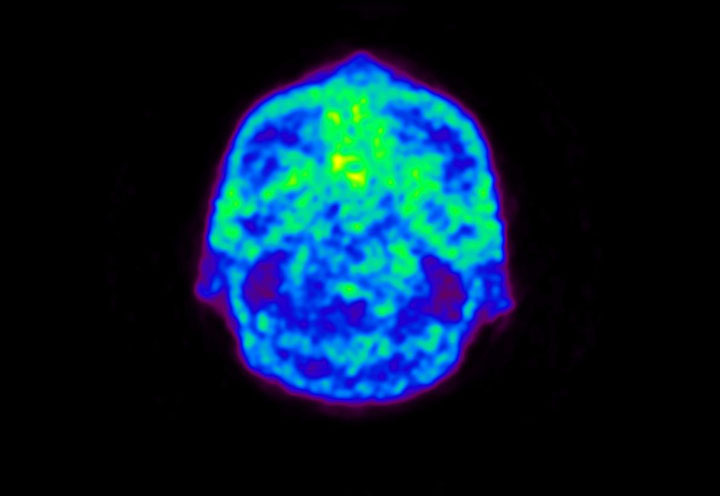

Head / Case5 : Amyloid

Axial

Courtesy : Kindai University Hospital

- Imaging protocol

- Injected dose: 4.27 MBq/kg, 18F-Flutemetamol

- Uptake time: 99 minutes

- Scan time: 20 minutes